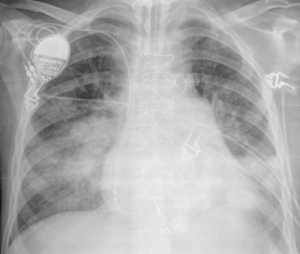

Los resultados de laboratorio mostraron hemoglobina de 88 g/l (8,8 g/dl), plaquetas 45 000 células/μl, leucocitos 7200 células/μl (linfocitos 240 células/μl), proteína C reactiva 254,7 mg/l (25,4 mg/dl) y antigenemia para citomegalovirus positivo. La radiografía de tórax mostró infiltrados pulmonares bilaterales (figura 1). Se inició tratamiento antibiótico de amplio espectro y ganciclovir. Dos días después de su ingreso, la detección del antígeno galactomanano de Aspergillus en suero y el lavado broncoalveolar resultaron positivos y se añadió voriconazol y caspofungina. Sin embargo, el paciente evolucionó rápidamente hacia un shock séptico y murió en cinco días. La necropsia mostró aspergilosis diseminada en los pulmones, los ganglios mediastínicos, la tiroides y en el injerto (figura 2) asociada con infección por citomegalovirus pulmonar y esofágica.

Figura 2. Examen posmuerte del injerto renal que muestra aspergilosis invasiva. Las flechas apuntan a hifas en el glomérulo. Técnica de plata, x400.